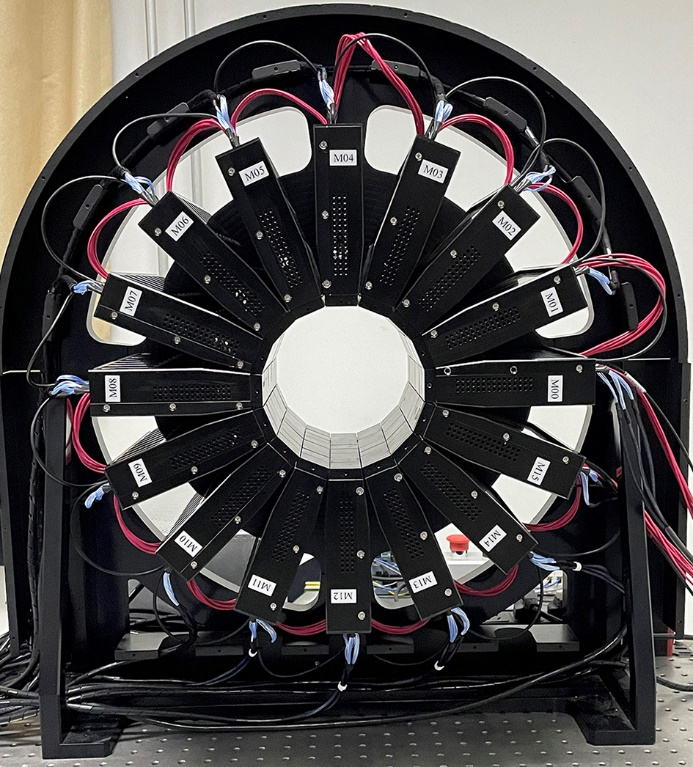

核技术应用研究中心团队攻克了长轴PET成像中灵敏度与空间分辨率相互制约的难题,成功研制全球首台兼具长轴向视野与高灵敏度的动物专用PET系统。该设备核心参数为:内径142 mm,轴向长度213 mm。依据国际标准NEMA NU 4-2008测试,其空间分辨率达0.88 mm(国际同类最优水平),系统灵敏度突破10.31%(超现有长轴设备30%以上),大鼠全身成像计数率高达682 kcps。通过优化晶体阵列排布和深度效应补偿算法(图1),显著提升大视野成像的信噪比与定量精度。

基于该设备成功实现了SD大鼠全身动态代谢成像(图2),成像结果清晰呈现了18F-FDG示踪剂从尾静脉注射后,经心脏循环至肝肾代谢的全过程,在单台设备上经单次扫描完成了大鼠多器官药代动力学连续监测。该技术突破为多靶点示踪成像、肿瘤转移机制研究及新药疗效评估提供了高精度研究平台,相关技术已申请国家发明专利3项。

图1 长轴动物PET扫描仪